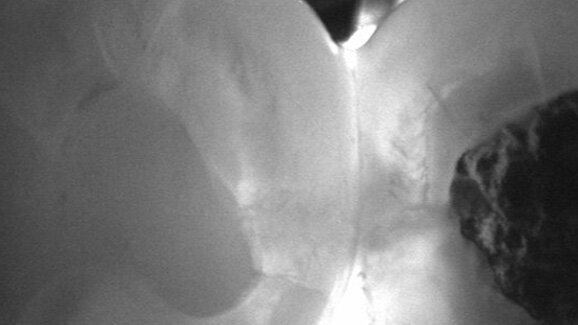

Die visuelle Untersuchung stellt immernoch die wichtigste Methode dar, um einfach und schnell Karies zu erfassen. Dennoch weist die visuelle Diagnostik, insbesondere im Approximalbereich, erhebliche Schwächen auf, sodass ergänzende Verfahren notwendig sind. Als Goldstandard hat sich hier die Bissflügelröntgenaufnahme etabliert. Seit einigen Jahren existiert mit der Nahinfrarot-Transillumination zudem eine neue Methode, um verlässlich kariöse Läsionen ohne Röntgenstrahlen darzustellen.

Im Webinar wird Priv.-Doz. Dr. Kühnisch, wissenschaftlicher Mitarbeiter an der Poliklinik für Zahnerhaltung und Parodontologie der Ludwig-Maximilians-Universität München, über das Potenzial der Methode sowie über eigene Forschungsergebnisse und die bisherigen klinischen Erfahrungen mit der Nahinfrarot-Transillumination berichten. Zudem wird das Verfahren mit etablierten Methoden der Kariesdiagnostik verglichen und typische Behandlungsstrategien für die einzelnen Läsionsstadien dargestellt.